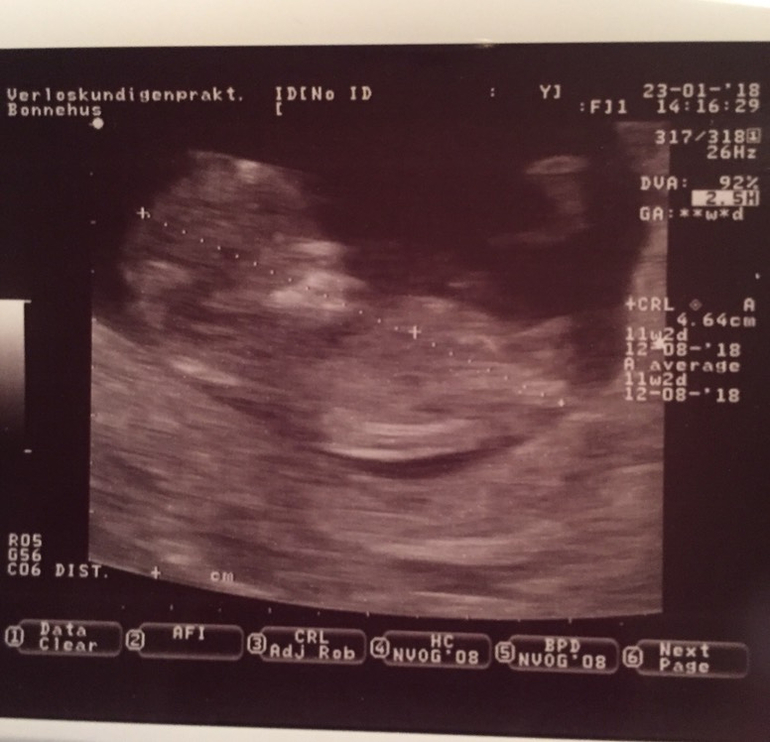

Это наше вчерашнее УЗИ